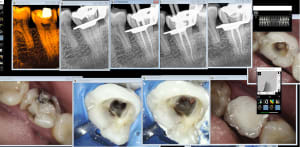

zoom_1570258573_suxrtb.jpg

zoom_1570258527_nvj0tg.jpg

zoom_1570258095_wh88wn.jpg

5A1ED2F3-46A0-45CF-8A09-ED06780C966D_dy9y3z.jpg

B4FABAC8-3F0A-44D1-A45E-D18E22A95ACB_zudxel.jpg